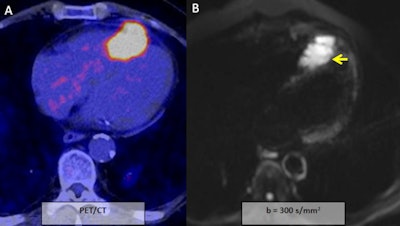

A 60-year-old man with head and neck squamous cell carcinoma, syncope, and negative T waves in the anterior wall. During the initial examination a hypermetabolic lesion in the apical septum and apex of the right ventricle was seen (A). It shows severe restriction to DWI (apparent diffusion coefficient: 0.73 x 10-3 mm2/s; B, C, and D; yellow arrows). Mild hyperintensity in T2 short tau inversion recovery (F; blue arrow) and heterogeneous enhancement (E; red arrow). All images courtesy of Dr. Jordi Broncano Cabrero.

A 60-year-old man with head and neck squamous cell carcinoma, syncope, and negative T waves in the anterior wall. During the initial examination a hypermetabolic lesion in the apical septum and apex of the right ventricle was seen (A). It shows severe restriction to DWI (apparent diffusion coefficient: 0.73 x 10-3 mm2/s; B, C, and D; yellow arrows). Mild hyperintensity in T2 short tau inversion recovery (F; blue arrow) and heterogeneous enhancement (E; red arrow). All images courtesy of Dr. Jordi Broncano Cabrero.Myocardial infarction is defined as myocyte death secondary to prolonged ischemia due to overwhelmed cellular repair mechanism by inadequate blood supply to the myocardium (the ischemic cascade). Complete necrosis occurs between two and four hours after the onset of the coronary blood flow impairment.